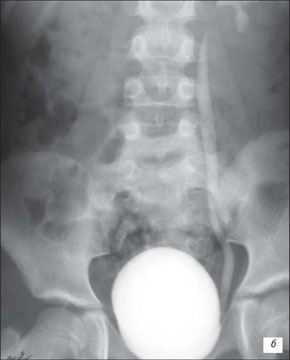

Рентгенограма хворих з СМР

При 1‑й степені закид контрасту з сечового міхура походить тільки в нерозширений сечовід.

При 2‑й степені заповнюють нерозширений сечовід і нерозширений чашечко-мискова система (ЧМС) нирок.

При 4‑й степені і вони стають заокругленими.

При 5‑й степені характеризується масивною делятацією і звивістю верхніх сечових шляхів.

Висхідна цистографія

На даній рентгенограмі спостерігаємо активно-пасивний міхурово-сечовий рефлюкс зліва 4 ступені. Виражена дилатація чашечко-мисочкової системи, деформація чашок.

а – у фазі максимального наповнення сечового міхура, пасивний рефлекс; б – у фазі сечовипускання, активний рефлекс.